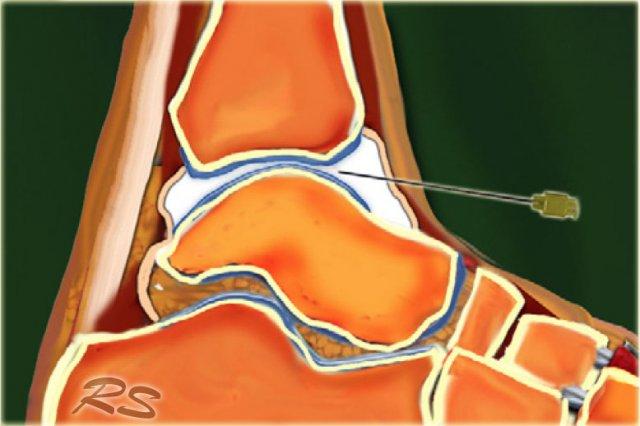

Tibiotalar joint

CT hoặc MR chụp khớp cản quang có thể được sử dụng để đánh giá tổn thương dây chằng, tổn thương xương sụn hoặc sụn khớp, đánh giá các dị vật tự do hoặc đánh giá sự ổn định của các tổn thương xương sụn.

Để tiêm vào khớp cổ chân (khớp chày-sên), bệnh nhân nằm ngửa với bàn chân ở tư thế gấp lòng nhẹ.

Mặt trong của khớp chày-sên được khảo sát ở phía trước bằng siêu âm để xác định vị trí thích hợp cho việc tiêm, đồng thời kiểm tra xem có dịch khớp quá mức hay không.

Chúng tôi sử dụng đầu dò mảng cong nhỏ 8 MHz, nhưng nếu muốn, có thể sử dụng đầu dò mảng tuyến tính 18-12 MHz. Trục dài của đầu dò được giữ trong mặt phẳng đứng dọc.

Kim tiêm, thường là cỡ 22 (dài: 30 mm), được đưa vào dọc theo trục hình ảnh dài của đầu dò ở phía trong của khoang khớp trước, phía trong so với dây chằng chày trước, tránh các dây chằng và mạch máu.

Cần xác định vòm xương sên và bờ trước xương chày nhô ra. Kim được đưa vào khớp theo hướng từ đuôi lên đầu, dưới bờ bụng của đầu xa xương chày, hướng vào bề mặt khớp của đầu xa xương chày.

Cảm nhận được sự tiếp xúc và một lần nữa đảm bảo rằng đầu kim không chạm vào sụn xương chày và mặt vát của kim hướng vào trong khớp.

8-10 ml thuốc cản quang được tiêm vào khớp chày-sên và người ta thấy bao khớp phía trước phồng lên do dịch.

Không nên có sức cản khi tiêm hoặc đau mà bệnh nhân cảm thấy.